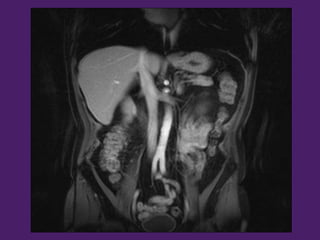

¡¡Y ahora…

más cortes!!

Bazo

Estómago

Pedículo

esplénico

Riñón izquierdo

Riñón

izquierdo

BazoCuerpo del

Páncreas

Arteria esplénica

Colon

Transverso

Tronco

celíaco

Lóbulo

izquierdo del

hígado

Aorta

abdominal

Arteria

mesentérica

superior

Vena Renal

izquierda